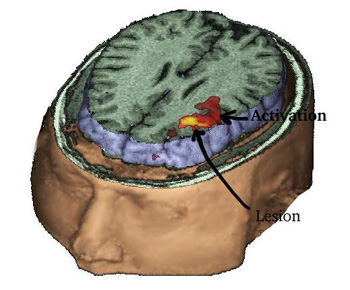

17 year-old right handed boy with intractable epilepsy of partial motor type. MRI showed signal abnormality in the left middle frontal gyrus consistent with cortical dysplasia.

MRI of the head with partial exposure of the brain and skull. An axial view located at the superior third of the inferior frontal gyrus demonstrates in red the activation obtained with a verb generation task. The yellow spot represents the lesion and is derived from a fluid attenuated inversion recovery (FLAIR) sequence, and rendered with the rest of images, revealing the relationship between the lesion and the eloquent areas.